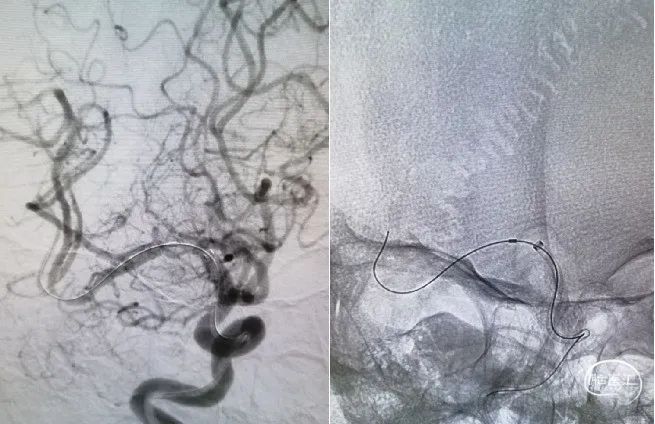

2mm*15mm Gateway球囊到位。

扩张后造影。

球囊扩张后随机Wingspan支架。

支架位置良好狭窄改善明显。